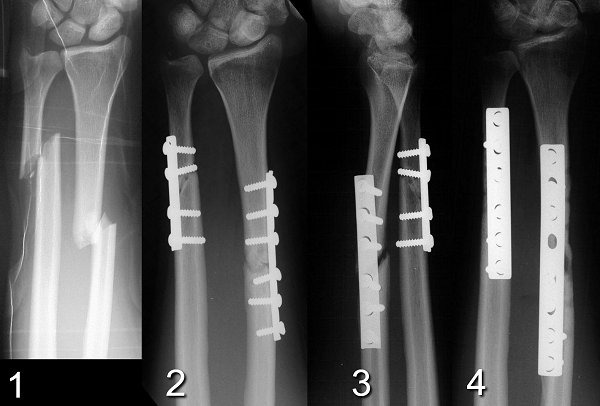

Figure Legend: Example of inadequate fixation.

This patient underwent open reduction and internal fixation of a displaced

both bone forearm fracture (1). Technical errors by the first surgeon include

use of semitubular plates, which have inadequate rigidity for this type

of fracture, and failure to achieve purchase of at least four cortices

on each side of the fracture (2). Each of these errors increase the

chance of nonunion. This patient developed nonunion with progressive

angulation of the radius (3) which required repeat fixation with bone graft

and compression plates (4).